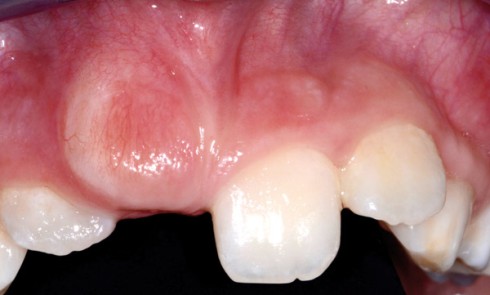

Article réservé à nos abonnés Prise en charge ortho-chirurgicale des incisives maxillaires incluses

Les incisives centrales maxillaires font leur éruption entre 7 et 8 ans et les incisives latérales maxillaires entre 8 et...